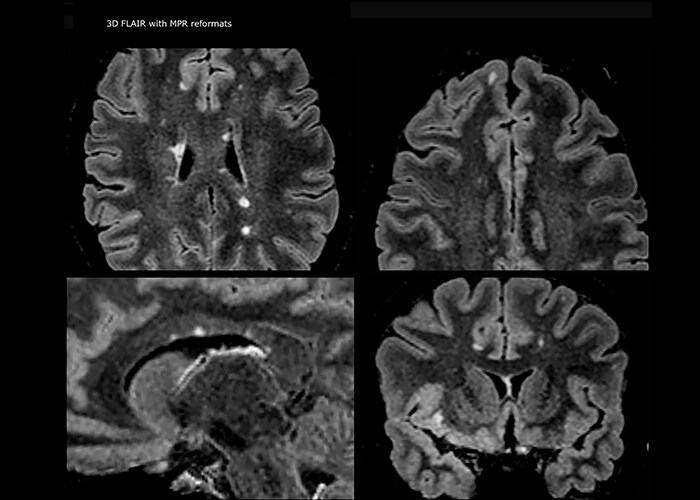

„Ingenia 3.0T liefert uns eine sehr gute Bildqualität mit hohem Signal-Rausch-Verhältnis, auch wenn wir die Auflösung ausreizen. Bei FLAIR-Bildern haben wir zum Beispiel eine isotrope Auflösung von 0,9 mm. Ingenia ermöglicht uns die Nutzung von 3D-T1-TSE mit BrainView, was eine bessere Empfindlichkeit als die 2D-Spinecho-Bildgebung[2] und die 3D-Gradientenecho-Bildgebung aufweist. Ingenia liefert auch hoch reproduzierbare Untersuchungen, was bei der MS-Bildgebung wichtig ist, damit Folgeuntersuchungen zu verschiedenen Zeitpunkten auf dieselbe Weise durchgeführt werden.“

Für die MS-Bildgebung im Gehirn nutzt Dr. Savatovsky 3D-FLAIR als Basissequenz, um die Läsionen darzustellen sowie die jeweilige Situation und die Läsionsbelastung zu beurteilen. „Wir zählen die Läsionen an jeder Stelle, um zu bestimmen, ob die Kriterien der Erkrankung erfüllt sind. Dafür wird eine T2-gewichtete Sequenz verwendet, weil unsere Neurologen diese gewohnt sind. Wir vergleichen die Läsionsbelastung unter FLAIR mit einer 3D-T1-Postkontrastsequenz, damit wir feststellen können, ob die Läsionen alt oder neu sind. In der Regel verabreichen wir das Kontrastmittel vor der Aufnahme des Patienten in das System, weil sich dadurch die Untersuchungsdauer verkürzt und die Visualisierung aktiver Läsionen möglich wird, die im Allgemeinen nach mehreren Minuten deutlicher dargestellt werden. Wenn sich eine differenzielle Diagnose als schwierig herausstellt, nutzen wir weitere Sequenzen wie die Suszeptibilitätsbildgebung, da einige fokale MS-Läsionen in der Mitte eine kleine Ader aufweisen[3].“